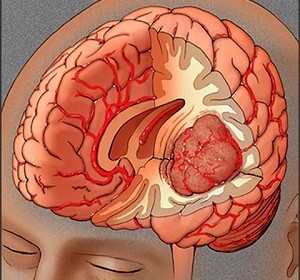

Triệu chứng thường gặp của u não

U não không có triệu chứng đặc trưng, hãy lắng nghe cơ thể để tìm kiếm [...]